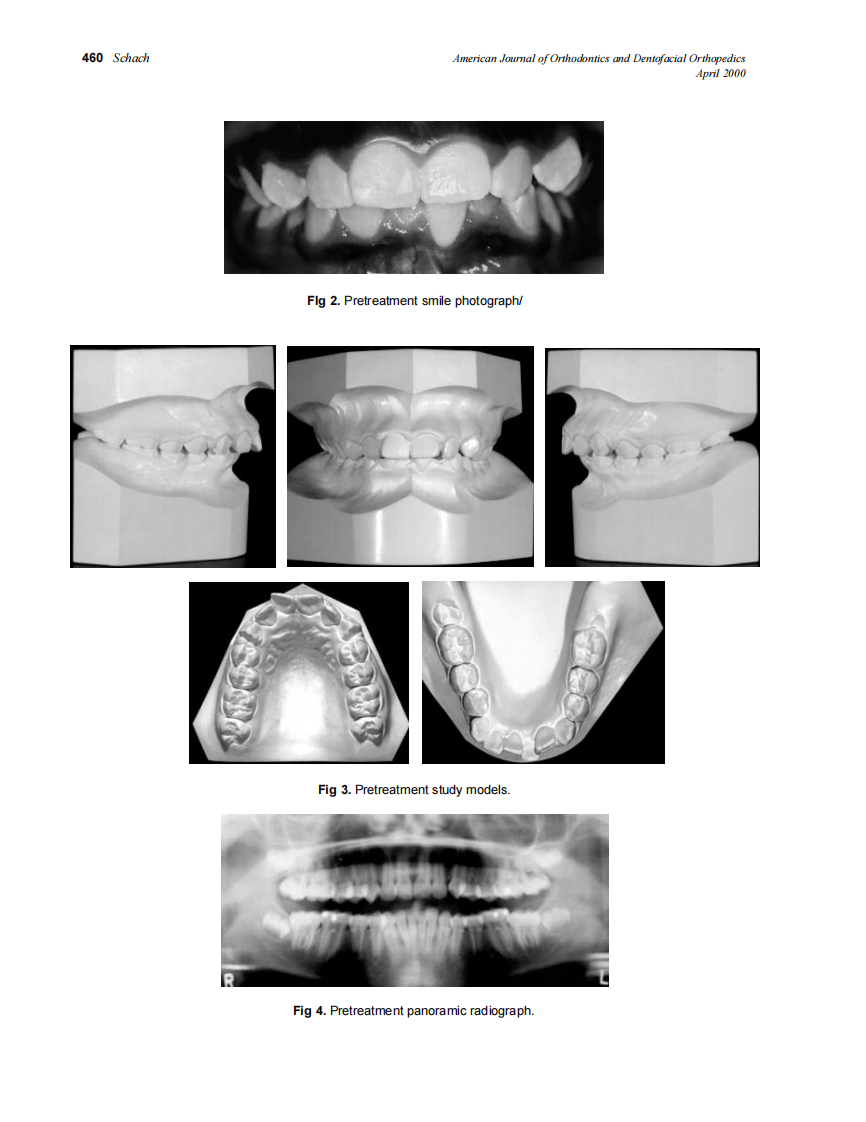

2000_117_4_459_464_Schach.pdf